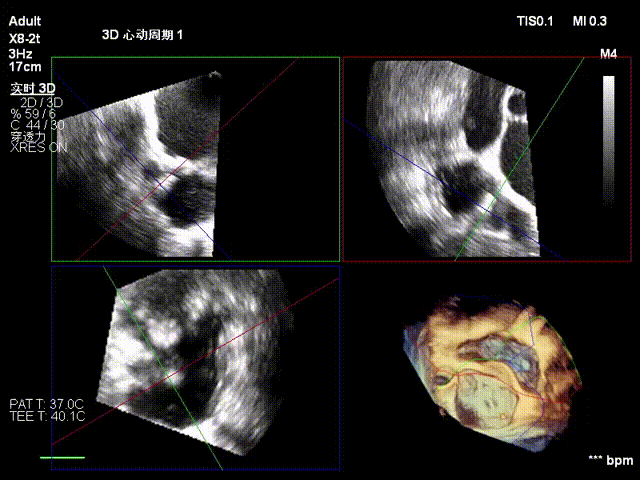

经右颈内静脉穿刺建立通路,置入18Fr鞘管,将K-Clip®输送系统送达右心房。依托三维经食管超声心动图(3D TEE)联合 DSA 双模态引导,经验精准定位瓣环,于后隔交界(P-S commissure)植入14T规格K-Clip®,前后交界(A-P commissure)植入16T规格K-Clip®,实现瓣环多点精准环缩。每枚夹子释放后,团队实时通过超声评估瓣叶对合及反流改善情况,严格遵循 “精准定位 - 锚定验证 - 安全解离” 的规范化操作流程,确认无瓣叶损伤、瓣口狭窄及心包并发症后,完成器械解离与撤出。

1. 术中基线评估三尖瓣反流程度